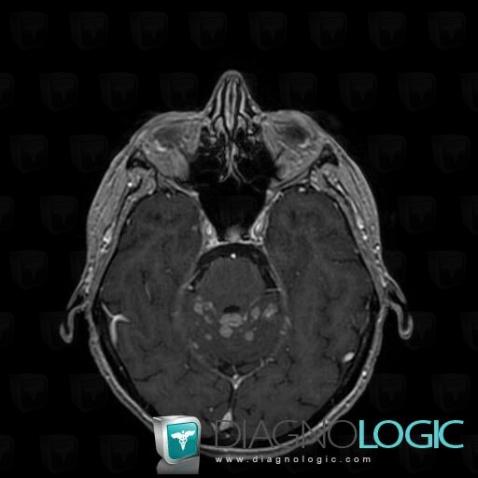

Voici les informations spécifiques à l'image clé ci dessus:

- Diagnostic Méningite carcinomateuse, Localisation(s) Région cortico sous corticale, comportant les gammes Lésion corticale

Voici les informations spécifiques à l'image clé ci dessus:

- Diagnostic Méningite carcinomateuse, Localisation(s) Région cortico sous corticale, comportant les gammes Lésion sous corticale